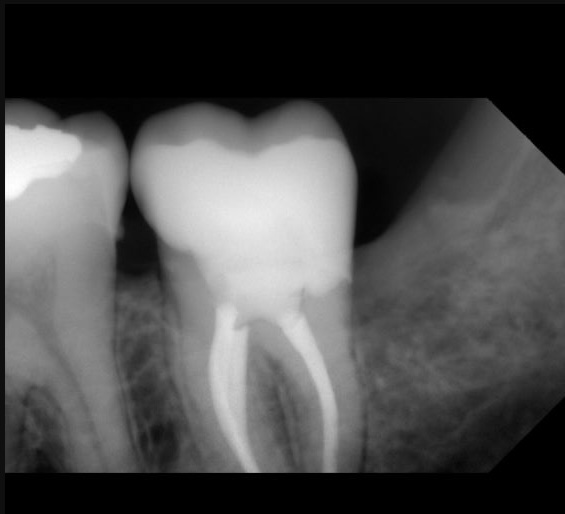

1.Gingivectomy

2.Root canal treatment